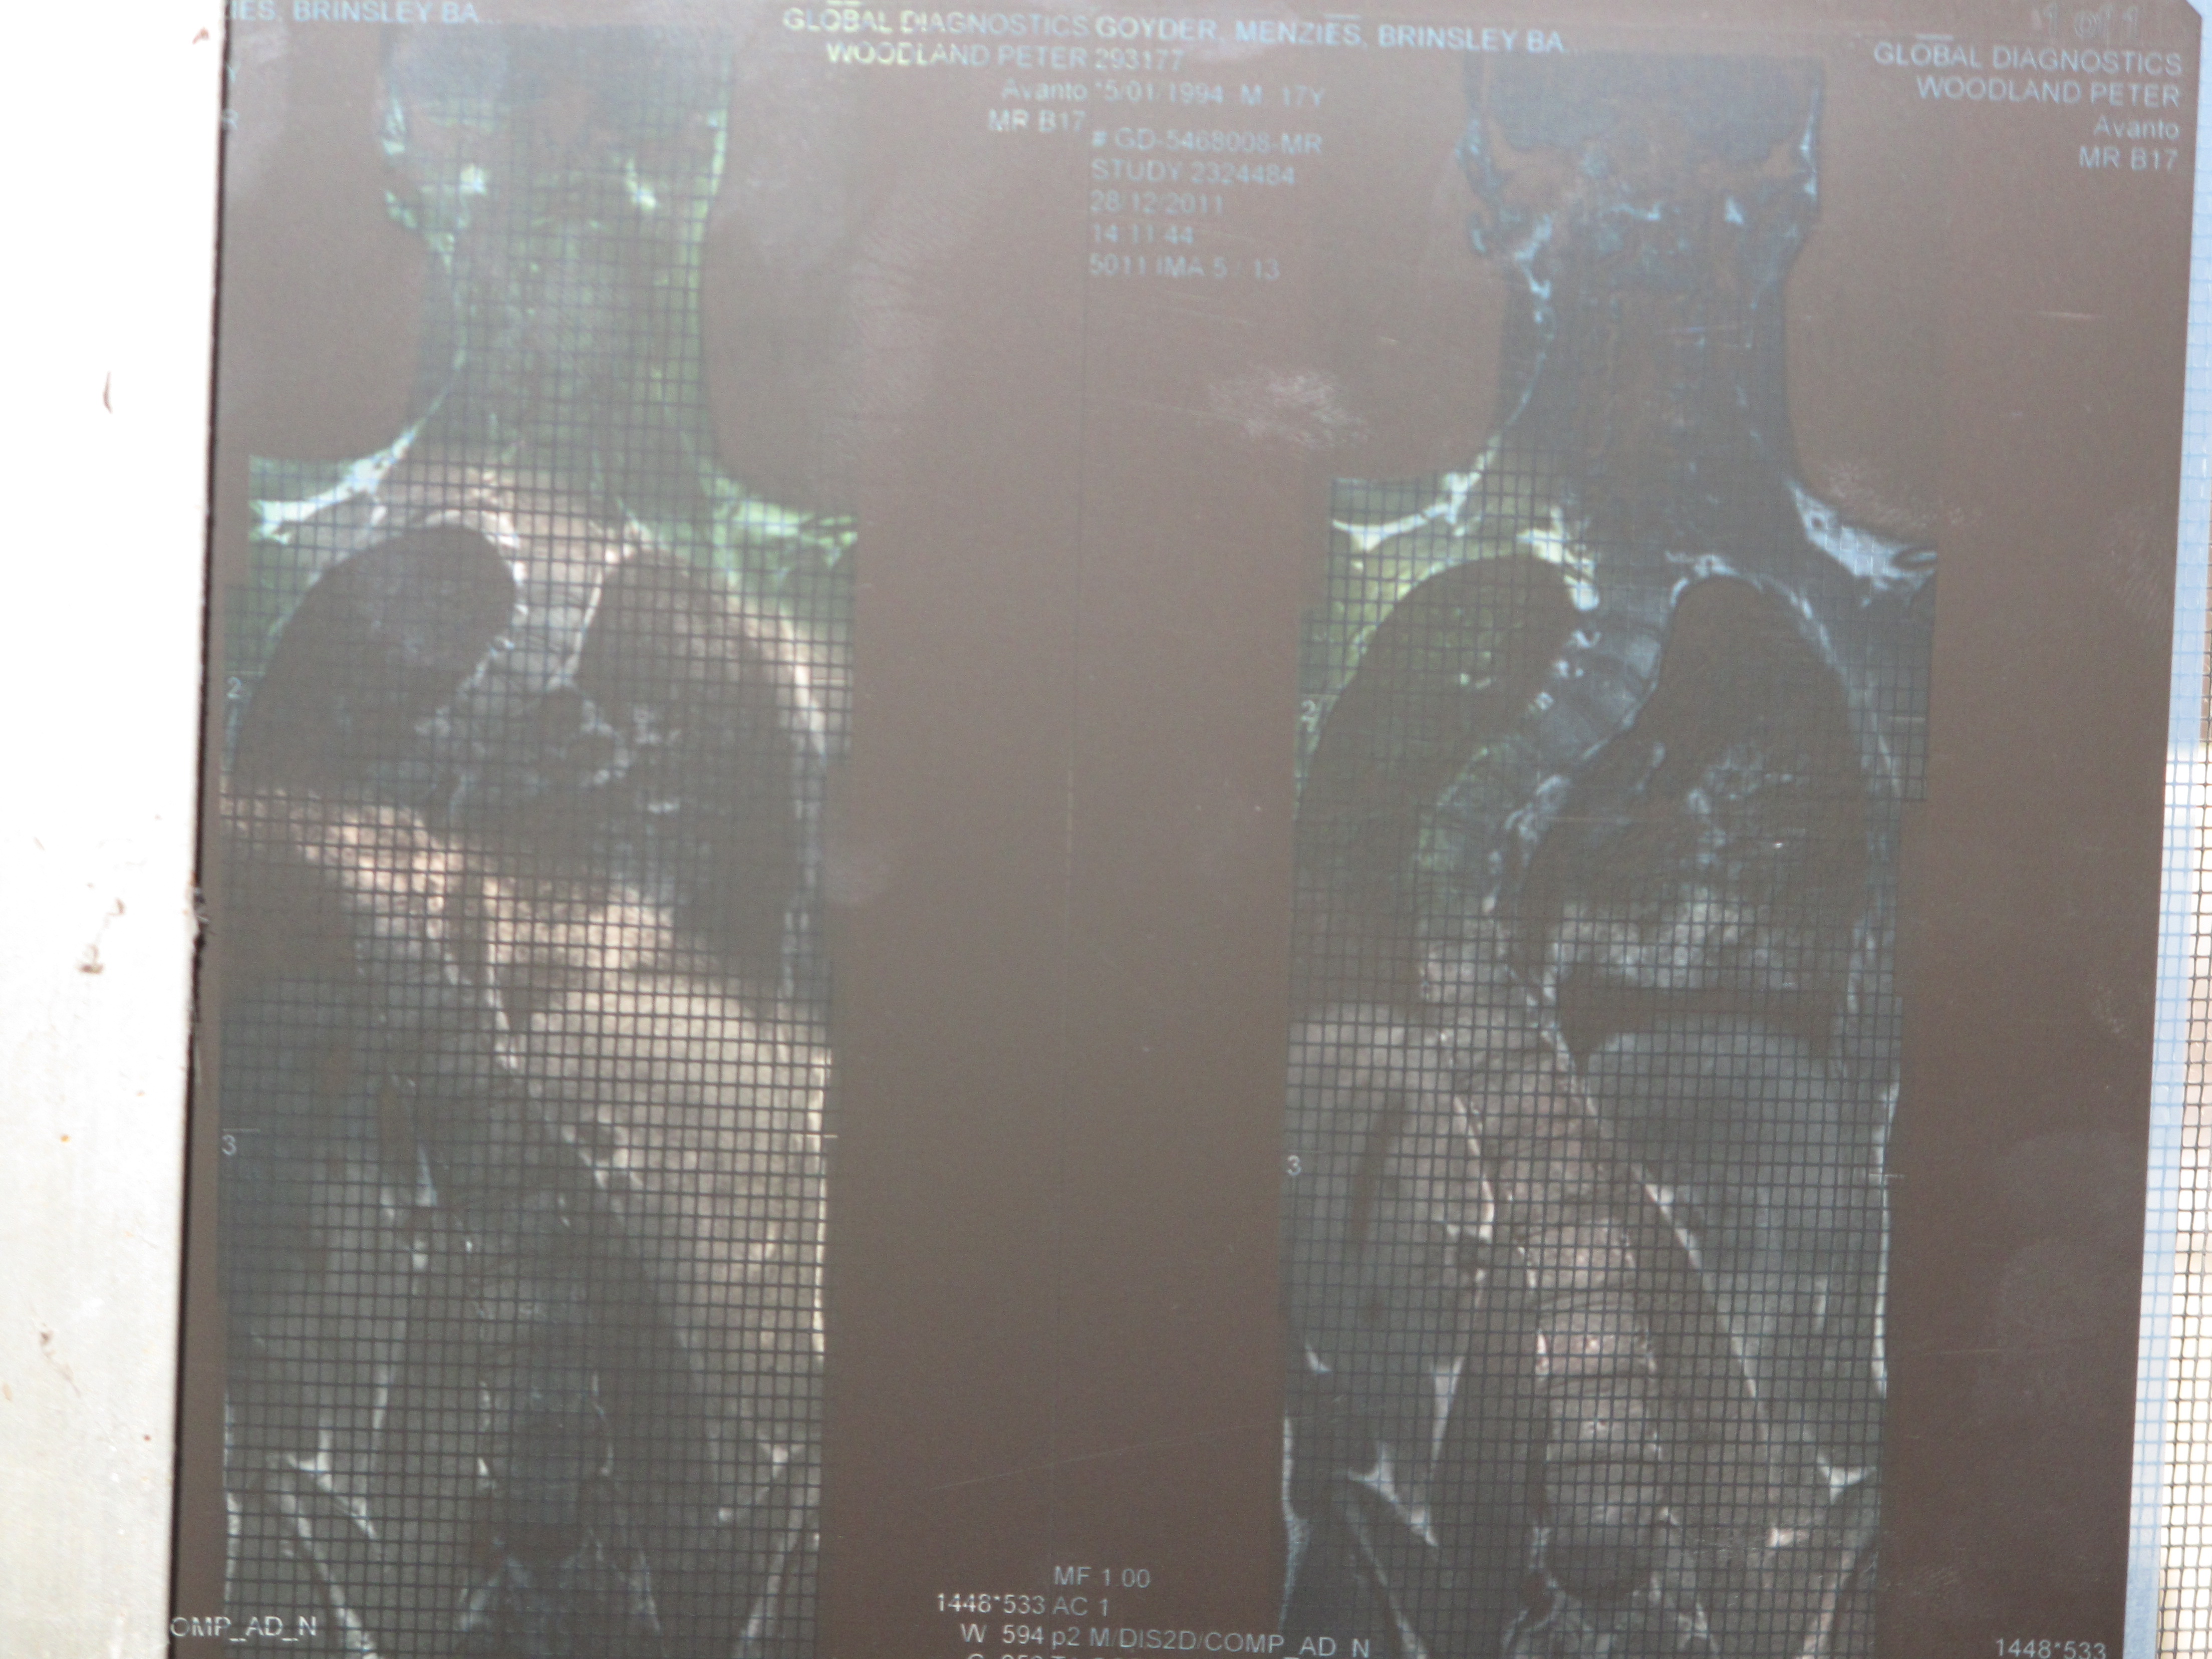

However, despite taking Son to numerous series’ of appointments with a chiropractor, physiotherapist, osteopath, kinesiologist, personal trainer and others (all of whom were wonderful and possibly prevented his scoliosis from getting even worse), the following X-ray speaks for itself. Surgery, which we hadn’t contemplated before, became a matter of inevitabilty rather than an option, so we saw a surgeon and Son was told he would have to have surgery and that he must stop playing football immediately. As this was two days before a school football trip in which Son was the star attraction (of course he wasn’t the star attraction, but I’m his mother so I like to say things like that), the devastation of this news was difficult to deal with and I will never forget Son’s sobs after that appointment.